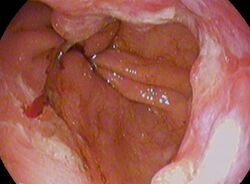

| Endoscopic image of an esophageal adenocarcinoma | |

Endoscopic image of Barrett esophagus – a frequent precursor of esophageal adenocarcinoma

Endoscopy and radial endoscopic ultrasound images of a submucosal tumor in the central portion of the esophagus